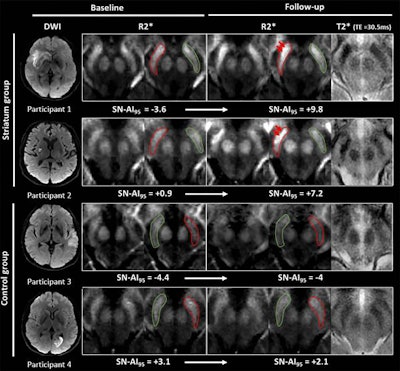

MR images show examples of visual R2* modifications within substantia nigra at baseline (24-72 hours after stroke) and at one-year follow-up in striatum (participants 1 and 2) and control groups (participants 3 and 4). Axial R2* maps are enlarged at mesencephalon level and one of the individual T2* echoes also is shown at follow-up. The substantia nigra is segmented in red ipsilateral to infarct and in green contralateral to infarct. Images without outlines are also shown. Brighter R2* spots are pointed with red arrows. Asymmetry index of 95th percentile of R2* within substantia nigra (SN-AI95) measured in these participants are indicated for reference. Participants 1 and 2 show marked asymmetry of R2* within ipsilateral substantia nigra at follow-up, compared with baseline after infarct involving entire striatum (participant 1) or limited to putamen (participant 2). Asymmetry also is visible on individual T2* echo at follow-up. Conversely, no asymmetry was observed in participants 3 and 4 sparing striatum. Images courtesy of Radiology.Linck and colleagues also observed an association between high iron content and poor long-term physical outcomes for stroke patients, particularly when increased iron levels were found on the same side of the brain where the infarction occurred. For example, follow-up tests showed reduced performances of patients when they tried to use their nondominant arms and in a 10-mile walking test.